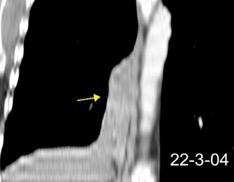

Triada de Garland

Ganglios paratraqueales derechos e hiliares bilaterales

95% de pacientes tienen ganglios hiliares bilaterales aislados o con afectación mediastínica (espec. paratraqueal derecho).

Criado E et al. Pulmonary sarcoidosis: typical and atypical manifestations at high-resolution CT with pathologic correlation. Radiographics. 2010